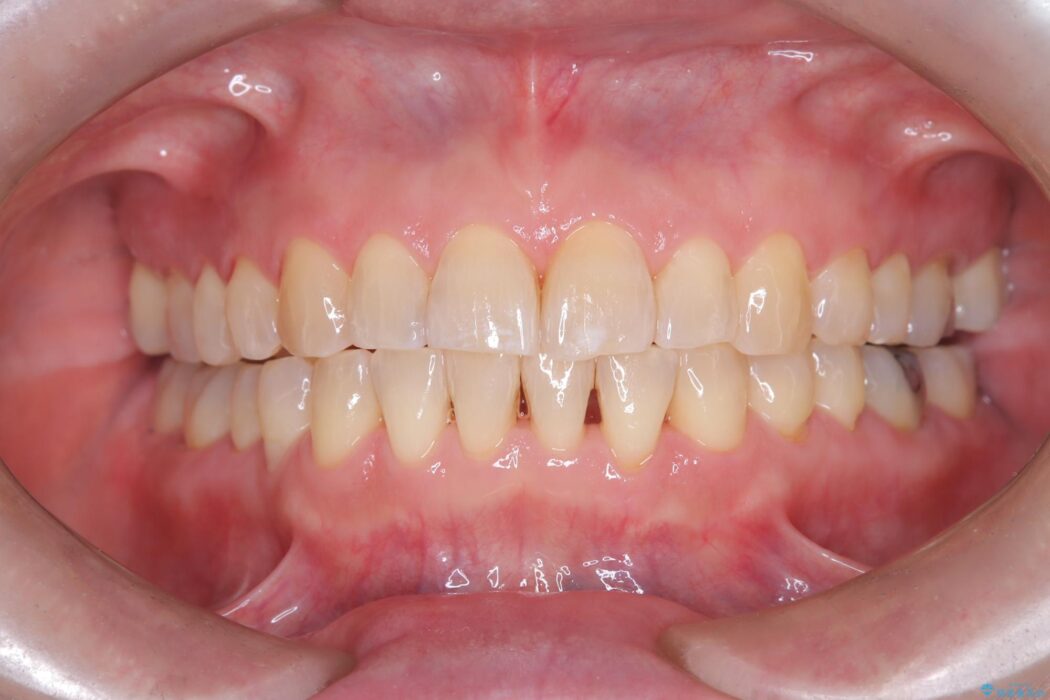

前歯のガタつきが気になるとご来院された患者様です。

ワイヤー矯正ならではの確実な歯のコントロールにより、当初の計画通り約1年という短い期間で、前歯のガタつきが解消。見た目が美しく整っただけでなく、清掃しやすい機能的な歯並びを獲得していただけました。